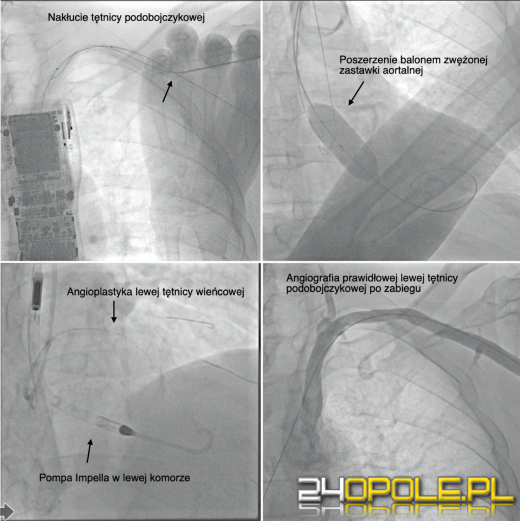

(Fot. USK Opole)

Z dostępu przez tętnicę podobojczykową, najpierw poszerzono zwężoną zastawkę aortalną, następnie tą samą drogą wprowadzono pompę do serca (Impella), po czym wykonano skuteczną angioplastykę lewej tętnicy wieńcowej.

Cały zabieg przeprowadzono bez chirurgicznego rozcinania tkanek i bez intubacji chorego. Tak złożonego zabiegu, wykonanego w tak nieinwazyjny sposób nie przeprowadzono jak dotąd w żadnym ośrodku kardiologicznym na świecie.

Dr Jerzy Sacha nie kryje satysfakcji z przeprowadzonego zabiegu - Przeprowadzony zabieg stanowi kolejny etap rozwijanej w naszym szpitalu małoinwazyjnej strategii operacyjnej z wykorzystaniem dostępu podobojczykowego - podkreśla.

W tym względzie USK w Opolu jest jedynym ośrodkiem w Polsce i jednym z kilku na świecie, które wytyczają szlak dla tej pionierskiej metody.